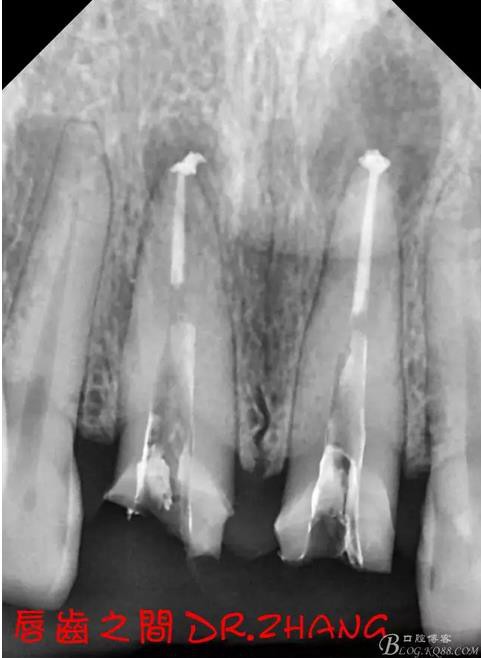

檢查:11 21金屬烤瓷冠 21根尖部牙齦紅腫 牙痛 叩(+++)冷刺激無反應(yīng) 11無不適癥狀 全口牙周情況良好

X片示11 21根管內(nèi)有高密度陰影 根尖低密度陰影

診斷:11 21慢性根尖炎

處理:21從修復(fù)體舌側(cè)打開通路 髓腔內(nèi)疑似纖維樁 高速和低速手機聯(lián)合去除樁核 在處理的過程中不斷拍片確認方向 去除樁核后拔髓針去除牙膠 只有一個標尖 膿液大量滲出 雙氧水和鹽水交替沖洗后 滲出減少 開放髓腔 隔日復(fù)診

復(fù)診:腫脹明顯消失 患者自訴感覺良好 溝通后決定拆除11 21兩顆烤瓷冠后重新修復(fù) 去冠器直接去冠 去除11根管內(nèi)的充填物 15#K銼疏通根管 11 21根長均為16MM平斷面 薩尼S3系統(tǒng)機擴至2S 期間不斷用氯己定和鹽水交替沖洗 吸潮紙尖干燥根管后06 25#試尖